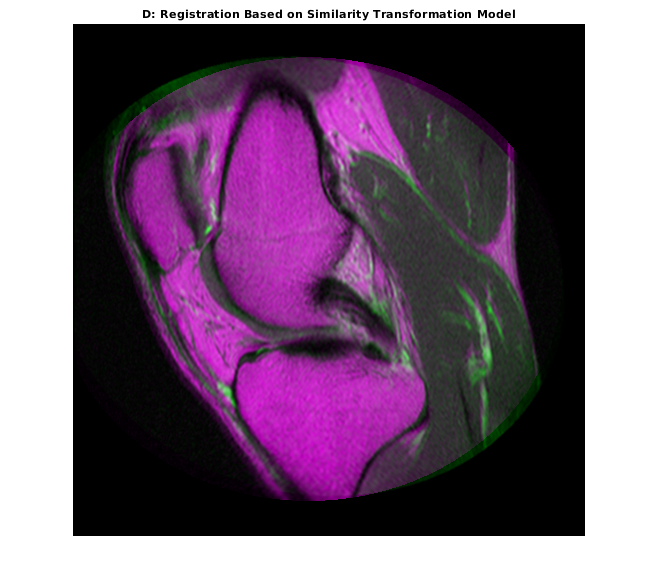

movingRegisteredRigid = imwarp(moving,tformSimilarity,'OutputView',Rfixed); imshowpair(movingRegisteredRigid, fixed) title('D: Registration Based on Similarity Transformation Model')

'T' свойство выходного геометрического преобразования задает матрицу преобразования, которая сопоставляет точки в перемещении в соответствующие точки в фиксированном.

tformSimilarity.T

ans = 3×3

1.0331 -0.1110 0

0.1110 1.0331 0

-51.1491 6.9891 1.0000